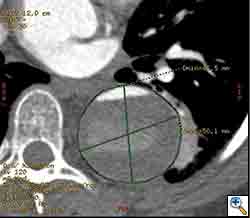

The patient was taken to the hybrid operating suite and a thoracic aortogram was performed. The aortogram confirmed the chronic Type B aortic dissection with a patent false lumen and a fenestration just beyond the left subclavian artery. An intravascular ultrasound (IVUS) was also performed of the entire aortic arch and descending thoracic and abdominal aorta. The IVUS also confirmed that there was an adequate proximal landing zone beyond the left subclavian artery consisting of normal aorta where we would be able to achieve adequate seal of the endovascular stent graft. The septal fenestration began approximately 1.5 cm distal to the left subclavian artery. The true lumen was compressed distally. (Figure 2) The celiac artery appeared to come off the true lumen. (Figure 3) The dissection extended into the superior mesenteric artery and the artery was perfused from both the true and false lumen. (Figure 4) The left renal artery came off the false lumen. (Figure 5) The right renal artery came off the true lumen.